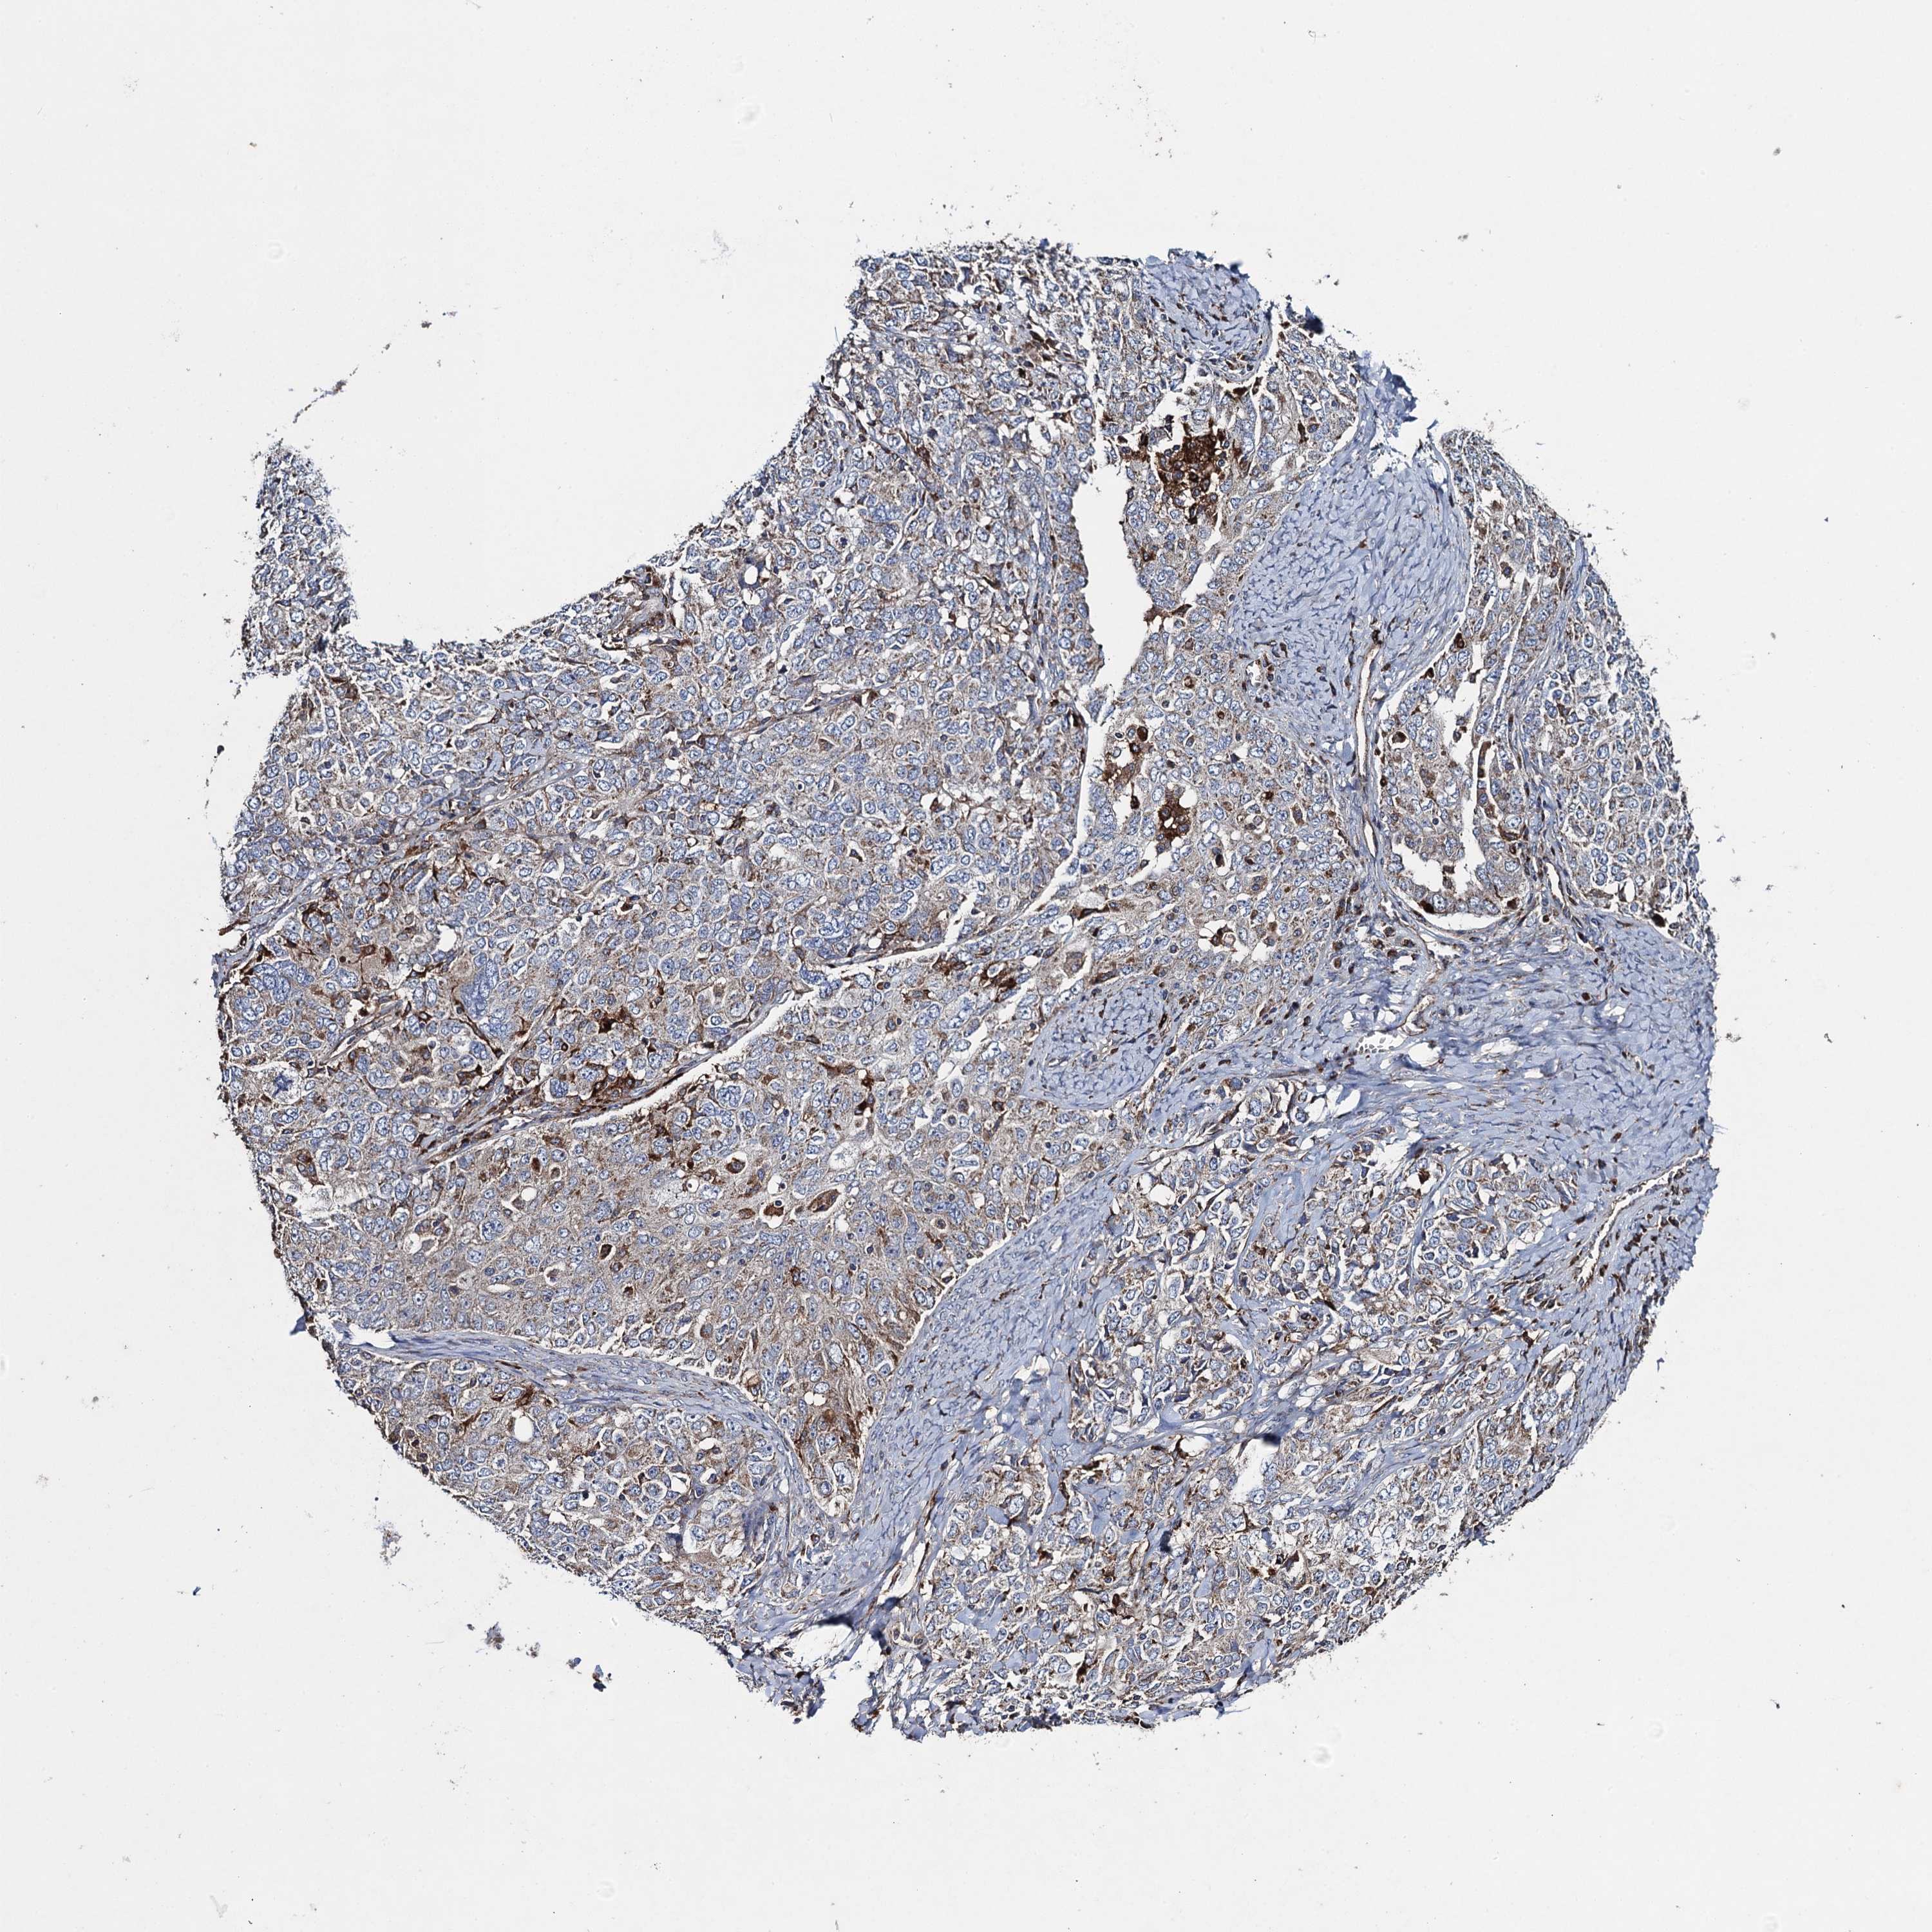

OVARIAN CANCER - Protein expressioni

A mouse-over function shows sample information and annotation data. Click on an image to view it in a full screen mode. Samples can be filtered based on level of antibody staining by selecting one or several of the following categories: high, medium, low and not detected. The assay and annotation is described here.

Note that samples used for immunohistochemistry by the Human Protein Atlas do not correspond to samples in the TCGA dataset.

Antibody stainingi

Antibody staining in the annotated cell types in the current human tissue is reported as not detected, low, medium, or high, based on conventional immunohistochemistry profiling in selected tissues. This score is based on the combination of the staining intensity and fraction of stained cells.

Each image is clickable and will lead to virtual microscopy that enables deeper exploration of all samples and also displays staining intensity scores, fraction scores and subcellular localization as well as patient and tissue information for each sample.

Antibody HPA041174

Antibody HPA041390

Cystadenocarcinoma, serous, NOS

Carcinoma, endometroid

Cystadenocarcinoma, mucinous, NOS

Carcinoma, NOS